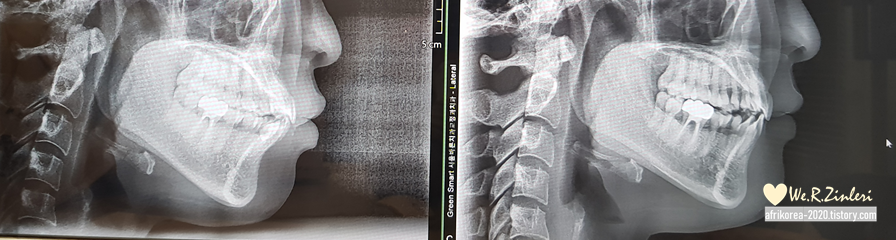

또 나름 신기했던 것은

옆모습의 변화다.

이 전에는 옆모습에서 불만이 느껴지는데

교저을 하면서 입이 들어가고

웃는 상으로 바뀌어 가는 것 같다.

내가 고의로 웃거나 한 것은 아닌데.